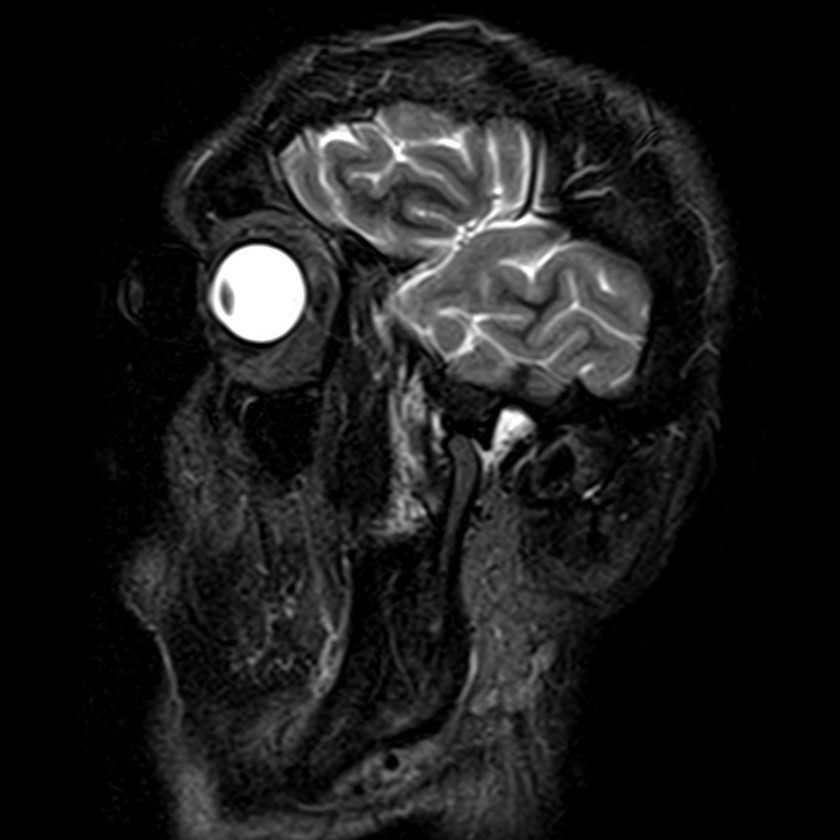

Височно-нижнечелюстной сустав является парным комбинированным суставом и имеет сложное строение. В него входят суставные ямки височной кости, суставные головки нижней челюсти и расположенные между ними хрящевые пластинки – мениски, выполняющие роль амортизаторов.

Чаще всего дисфункция височно-нижнечелюстного сустава обусловлена внутренним повреждением, смещением мениска и суставной головки нижней челюсти. Для определения степени смещения внутрисуставных структур выполняется функциональная проба с проведением МРТ в двух положениях:

Магнитно-резонансная томография является наиболее точным и эффективным методом диагностики поражения височно-нижнечелюстных суставов, так как позволяет получить детальную информацию о состоянии не только костей, но и связочного аппарата, хрящей, менисков, жевательных мышц, окружающих мягких тканей.

В клинике «Доступная медицина» можно пройти исследование МРТ височно-нижнечелюстного сустава на высокотехнологичном оборудовании. Клиника располагает новейшим томографом экспертного класса TOSHIBA VANTAGE TITAN 1,5 Тесла, который благодаря высокой индукции магнитного поля позволяет получать изображения исследуемой зоны в мельчайших подробностях. Томограф производит послойное сканирование области сустава и околосуставных мягких тканей, затем с помощью цифровых приложений преобразует полученные данные в трехмерные изображения превосходного качества.

При проведении магнитно-резонансной томографии на изображениях визуализируются: височная кость, головка мыщелкового отростка нижней челюсти, суставная щель. Помимо костных структур МРТ позволяет оценить состояние мягких тканей – внутрисуставного диска и связочного аппарата височно-нижнечелюстного сустава, жевательных мышц.